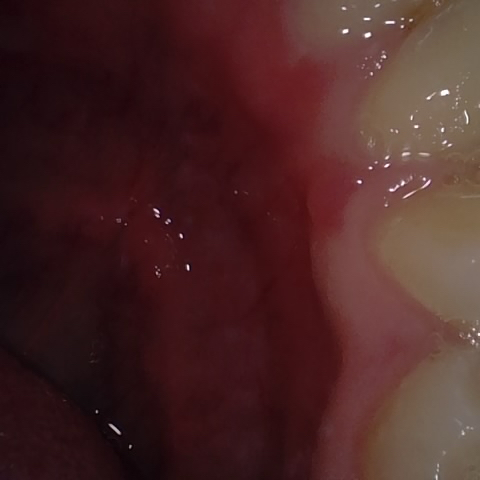

Annotated as "Good"